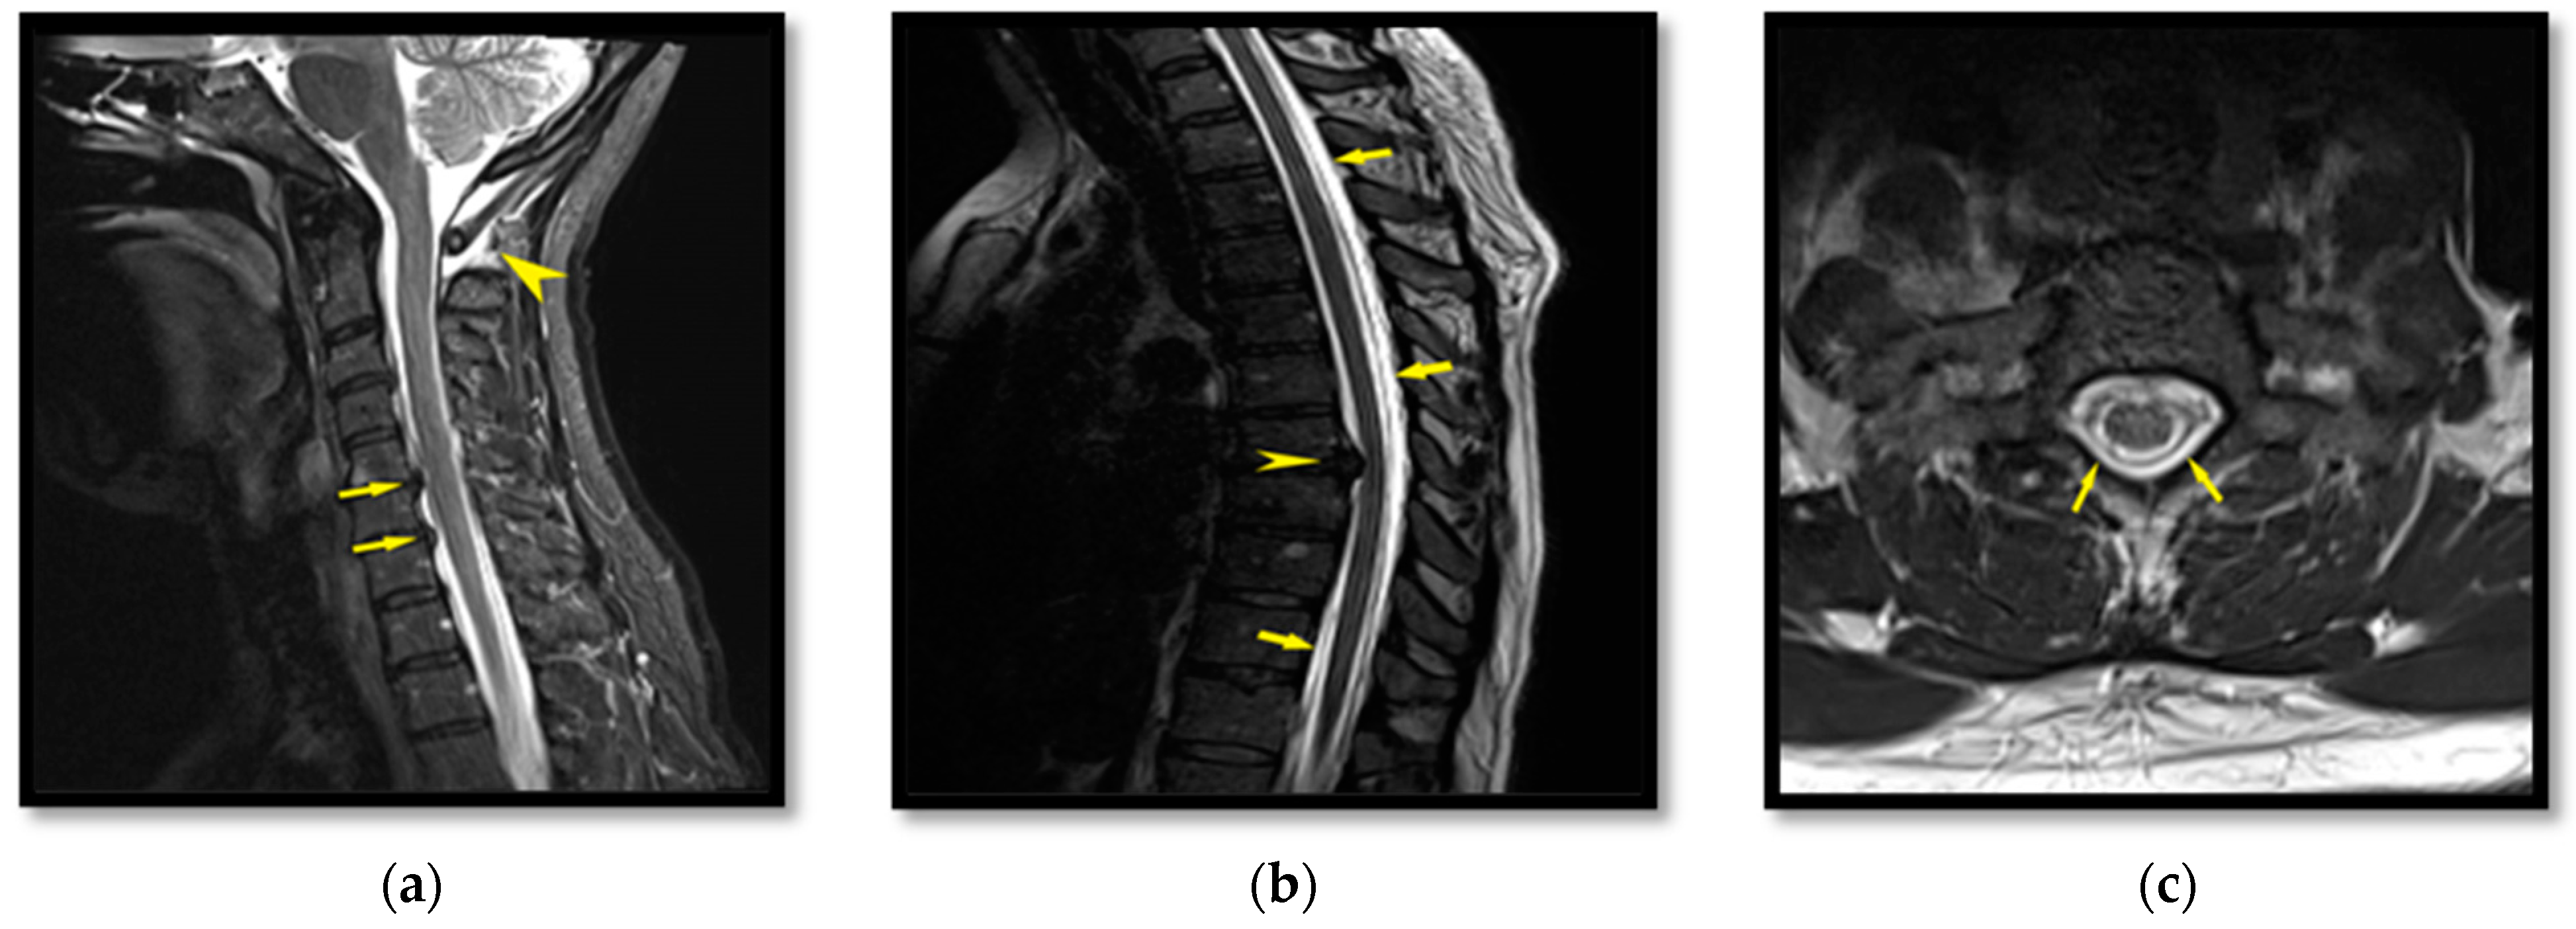

2.2. Patient II